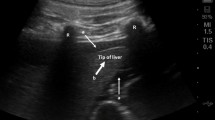

Correlating the results with the ablation effect based on a single pair of electrodes was challenging. Therefore, it was imperative to consider the impedance magnitude from all channels. In this study, we aggregate the relative changes in impedance magnitude-center from all channels, as shown in Fig. 7a. The tissue electrical impedance change magnitude and temperature changes under electrical impedance control during ablation are shown in Fig. 7b. The microwave source is deactivated at 161 s, 241 s, 301 s, 351 s, 431 s, and 481 s, respectively, to ensure the relative change in electrical impedance magnitude stay below 20, which is used as a reference threshold. After each deactivation of the microwave source, the electrical impedance change magnitude exhibits a declining trend, followed by a rapid increase upon reactivation. The coagulation zone measures 45 mm in length and 23 mm in width, with a total ablation time of 511 s. Before employing this method, Fig. 7c shows the experimental outcomes of thermal ablation on ex vivo porcine liver, revealing a significant presence of blackened, charred tissue in the central zone. As shown in Fig. 7d, the results from the control group utilizing electrical impedance change magnitude indicate minimal to no presence of charred tissue in the central zone. Hence, the electrical impedance detection method effectively prevented carbonization within the central zone.

Trends of electrical impedance change magnitude and temperature during MWA. (a) Superimposed results of relative changes in electrical impedance magnitude from channels 1 to 6. (b) Results of relative changes in electrical impedance magnitude from channels 1 to 6 after electrical impedance control. (c) Actual ablation effect before electrical impedance control. (d) Actual ablation effect after electrical impedance control.